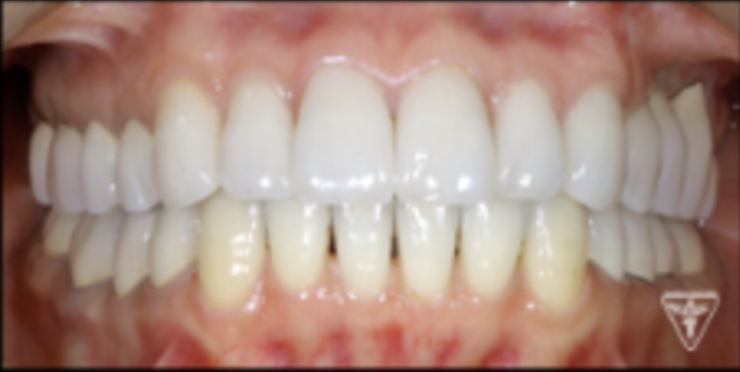

最終補綴物装着時

治療後